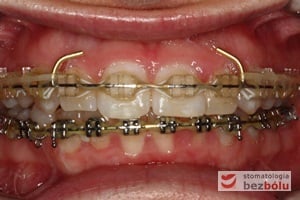

Leczenie bezekstrakcyjne z wykorzystaniem strippingu

Pacjentka lat 22 zgłosiła się do naszej placówki celem podjęcia leczenia ortodontycznego. Głównym oczekiwaniem pacjentki była poprawa estetyki uśmiechu oraz brak ekstrakcji zębów na drodze do jej uzyskania. Ze względu na liczne stłoczenia zębów w górnym i dolnym łuku, dość duży materiał zębowy w porównaniu z bazą kostną, a także zgryz przewieszony boczny prawostronny po dokładnej analizie cefalometrycznej oraz analizie modeli diagnostycznych zastosowano leczenie bezekstrakcyjne z wykorzystaniem strippingu jako alternatywy dla usuwania zębów, mającego na celu uzyskanie miejsca w łuku na uszeregowanie zębów. Po fazie aktywnego leczenia trwającego 18 miesięcy zastosowano leczenie retencyjne w postaci szyny retencyjnej w łuku górnym oraz retainera stałego w łuku zębowym dolnym klejonego od kła do kła.